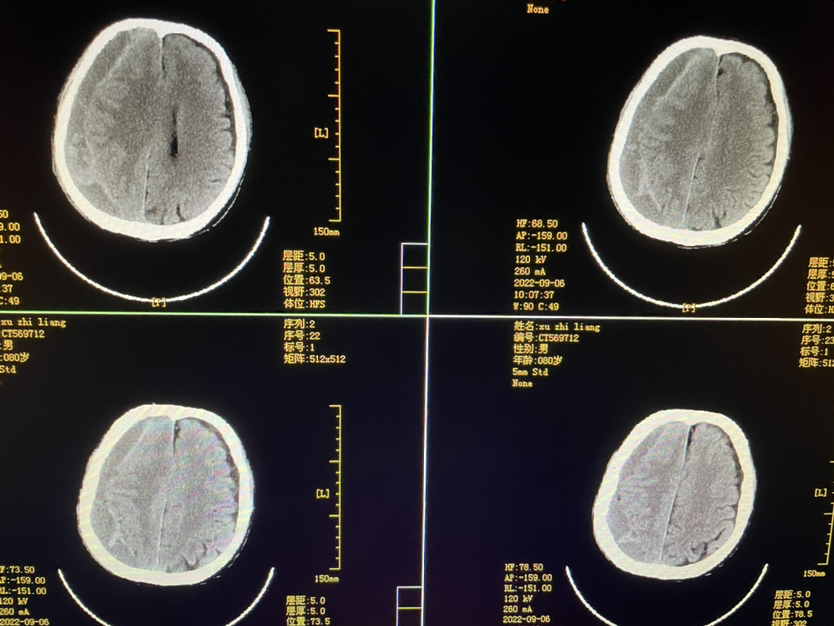

明确外伤史二月,80y,